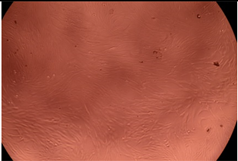

| Sample | Micrographs | ||

|---|---|---|---|

| 24 h | 48 h | ||

| Control |  |  | |

| F127 | 10 µg/mL |  |  |

| 50 µg/mL |  |  | |

| 100 µg/mL |  |  | |

| 200 µg/mL |  |  | |

| F127/PA = 10/1 (g/g) | 10 µg/mL |  |  |

| 50 µg/mL |  |  | |

| 100 µg/mL |  |  | |

| 200 µg/mL |  |  | |